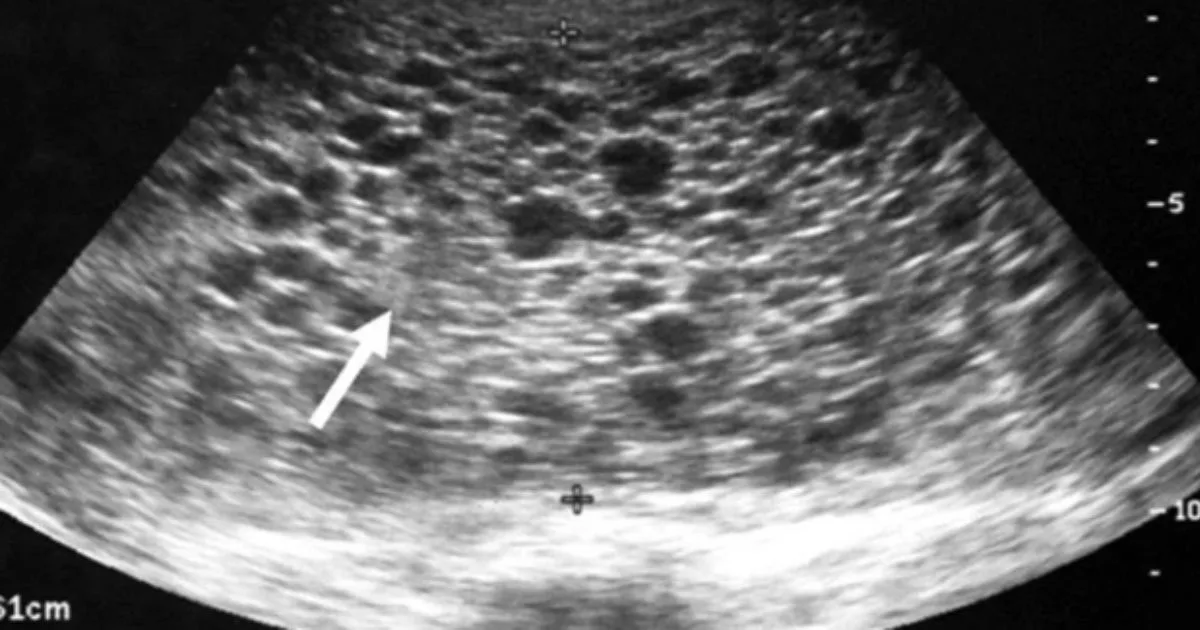

Keadaan ini berlaku apabila proses persenyawaan antara sperma dan ovum tidak normal. Akibatnya, tisu uri berkembang secara tidak terkawal dan membentuk kantung kecil berisi cecair yang dikenali sebagai hydatidiform mole. Janin sama ada tidak terbentuk langsung atau terbentuk tetapi tidak mampu hidup.

Tiada pembentukan janin berlaku langsung. Rahim dipenuhi sepenuhnya oleh tisu abnormal walaupun hormon kehamilan masih tinggi dan ujian kehamilan kekal positif.

2. Kehamilan Anggur Separa (Partial Mole)

Janin mungkin terbentuk, tetapi tidak sempurna dan biasanya tidak mampu hidup lalu gugur pada peringkat awal kehamilan.